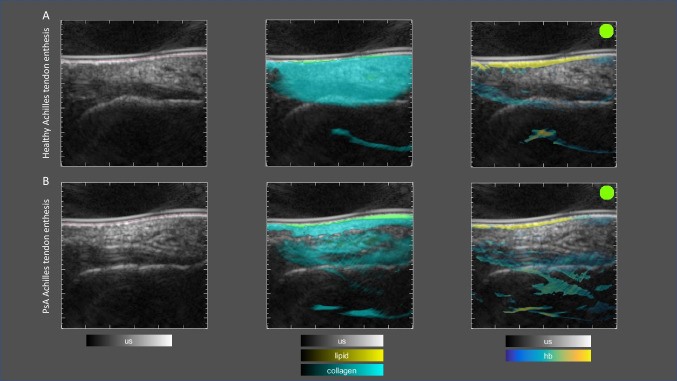

Purpose of review: Psoriatic arthritis (PsA) is a complex heterogeneous inflammatory disease that affects about one-third of patients with psoriasis. PsA leads to significant physical impairment and reduced quality of life. Therefore, early diagnosis and intervention are critical for improving long-term outcomes. The purpose of this review is to highlight the advantages of unconventional imaging methods in the diagnosis and management of PsA and to discuss recent advancements in imaging technology.

Recent findings: Conventional imaging methods, such as radiography, musculoskeletal ultrasound, and magnetic resonance imaging, have been instrumental in detecting structural joint damage and inflammation. However, these imaging modalities have several limitations, resulting in their inability to detect early disease changes. Recent advancements in imaging technology have led to the development of novel imaging modalities capable of characterizing not only early structural but also molecular aspects of disease activity. These cutting-edge approaches have been lately applied to both psoriasis and PsA patients, offering new insights into disease progression, the transition from psoriasis to PsA, and treatment responses. By providing more detailed and individualized assessments, unconventional imaging modalities may bring us closer to realizing the potential of personalized medicine in the management of PsA.